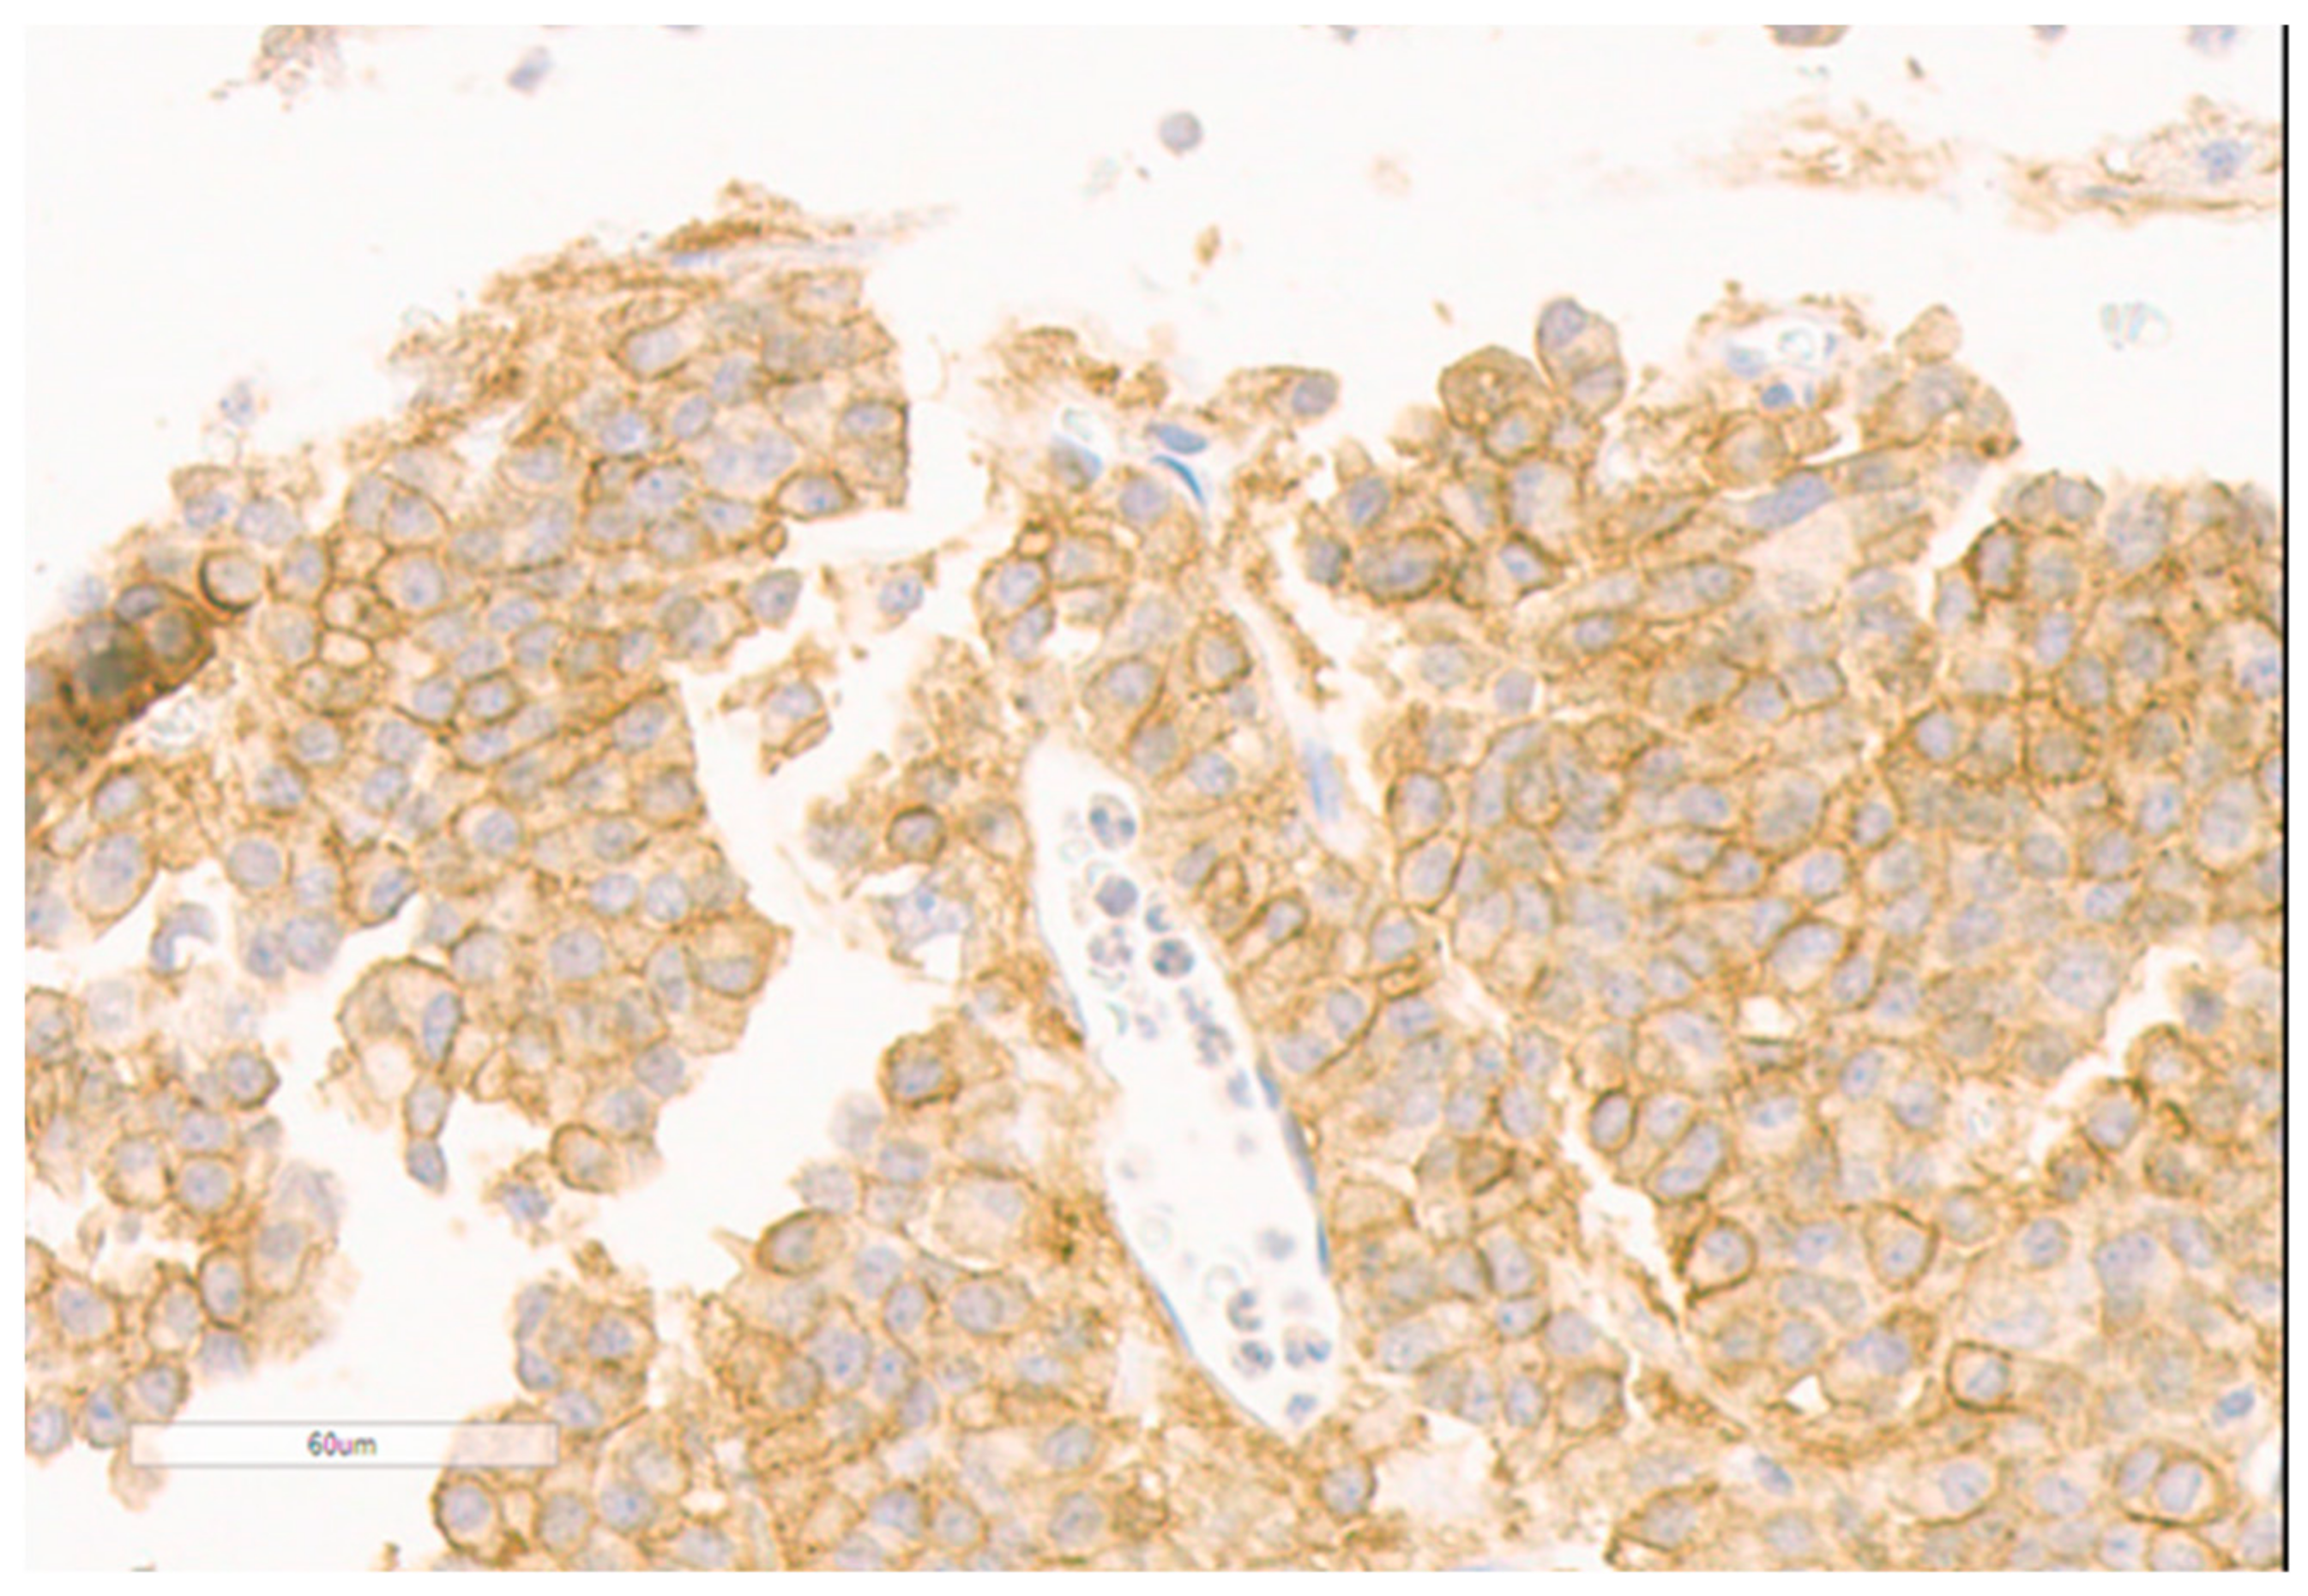

| Adenoma size | Macroadenoma (12 mm) | Macroadenoma (37 mm) |

| Histology | Densely granulated | Sparsely granulated, fibrous bodies |

| Ki67 | 5% | 5% |

| SSTR2 | IRS = 8 | IRS = 6 |

| SSTR5 | IRS = 6 | IRS = 8 |